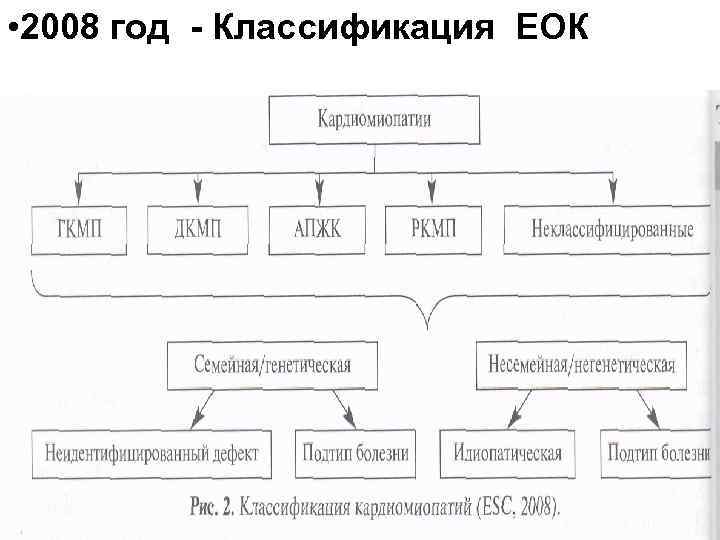

• 2008 год - Классификация ЕОК

• 2008 год - Классификация ЕОК